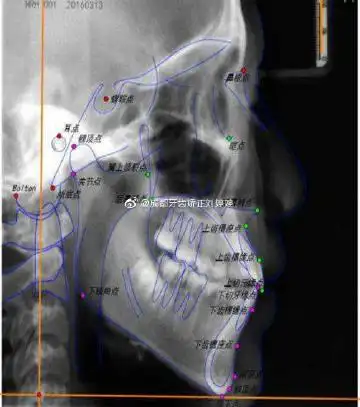

双侧颞颌关节强直

颞下颌关节强直,一般采取外科治疗,在手术前,需要明确诊断此病

去正畸时,拍片发现得了颞下颌关节紊乱